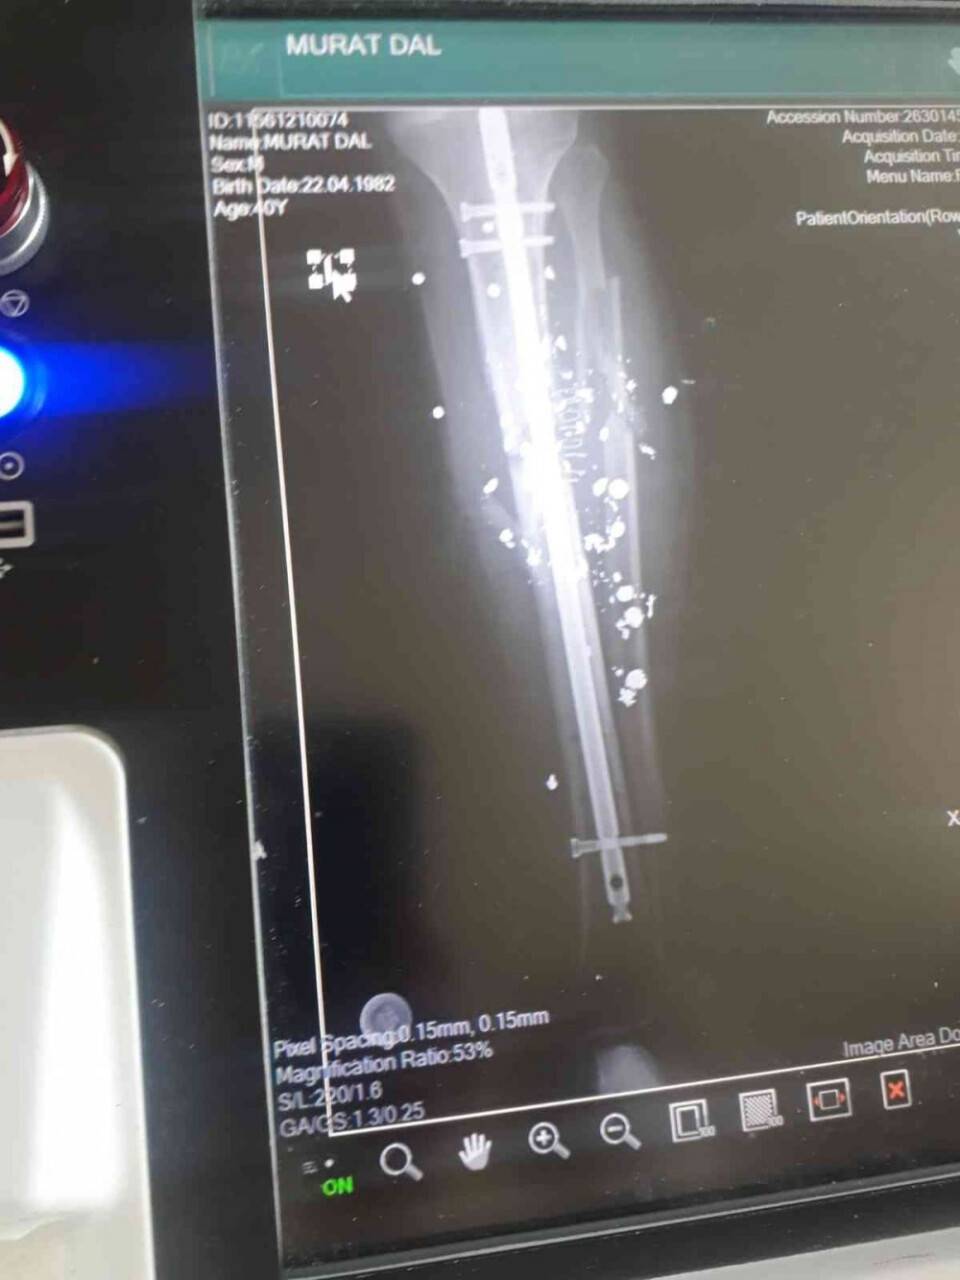

Geçtiğimiz Mayıs ayında 71 Evler Mahallesi Mehmet Akif Ersoy Sokak'ta abisi Cafer Dal ve yeğeni Ferhat Dal ile aralarındaki husumetten dolayı yaşadığı tartışma sonucunda Murat Dal, sol bacağından pompalı tüfek ile vurularak yaralandı. Yeğeni Ferhat Dal'ın pompalı tüfek ile yakın mesafeden açtığı ateş sonucu yaralandığını iddia eden Murat Dal, 2 ay boyunca yoğun bakımda tedavi gördü. Tedavi sürecinde 3 tane büyük ameliyat geçirdiğini belirten Dal, son ameliyatında kan kaybından dolayı kalbinin durduğunu ve doktorların çabasıyla tekrar hayata tutunduğunu söyledi. Ameliyatların ardından arkadaşının evinde konakladığını söyleyen Murat Dal, bacağının enfeksiyon kaptığını ve bir süre daha iyileşmemesi durumundan dizden aşağısının kesileceğini belirtti. Olayların ardından yeğeni Ferhat Dal'ın gözaltına alındığını, fakat çıkarıldığı mahkemede tutuklanmadığını belirten Murat Dal, olayın ardından şikayetçi olmasından dolayı da abisinden ve yeğeninden tehditler aldığını iddia etti.

Yeğeni tarafından pompalı tüfek ile vurulduktan sonra arkadaşının yanına yerleştiğini ve koltuk değnekleriyle dahi zorlukla hareket edebildiğini belirten 40 yaşındaki Murat Dal, gelirinin ve hiç kimsesinin olmamasından dolayı zor durumda olduğunu belirtti. Yoğun bakımda 2 ay geçirdiğini ve 3 ameliyata girdiğini belirten Murat Dal, kendisine ateş eden yeğeninin dışarıda elini kolunu sallayarak gezdiğini "Benim öz abim olan Cafer ve yeğenim Ferhat ile biz tartıştık. Sonra ben kızdım ve abimle tartıştıktan sonra çıktım oradan. Sonra yeğenim arkamdan ateş etti, beni vurdu. Hiçbir sebebi olmadan boştan yere beni pompalı silahla vurdu. Bu suçtan dolayı hiçbir şekilde kimse tutuklanmadı. Ben 2 ay hastanelerde kaldım. Bir ay yoğun bakımlarda yattım. Yoğun bakımda kaldığım süreçte 3 tane ameliyat geçirdim. 3'üncü ameliyatımdan sonra da şu an geldim. Sağ olsun bir arkadaşım bana yardımcı oldu. Beni evine aldı. Şu an onun yanında kalıyorum, Allah razı olsun. Hiçbir gelirim yok. Hiç kimsem yok. Şu anda çok zor durumdayım. Bu insanlar hâlâ geziyor dışarılarda elini kolunu sallayarak" ifadeleriyle dile getirdi.

Bacağının enfeksiyon kaptığını ve tekrar gireceği ameliyatın sonucunda ilerleme kaydedilemezse dizden aşağısının kesileceğini belirten Murat Dal, abisi ve yeğeni tarafından da hala tehdit edildiğini ifade ederek şunları söyledi:

"Hiçbir şekilde yani ben kötü bir söz söylemedim. Kavga etmedim, bağırmadım çağırmadım. Beni boştan yere vurdular. Şu anda ayağım çok zor durumda. Çok kötü bir durumdayım. Lütfen bana yardım edin. Sizden yardım istiyorum. Şu an dördüncü ameliyatım veyahut da beşinci ameliyatı olmak üzereyim. Şu an ayağım enfeksiyon kapmış. Ayağımı kaybetmek üzereyim. Beni hala şu anda telefon arıyorlar. İşte "Niye böyle dedin, bizi söyledin?" diye beni tehdit ediyorlar. Ben çıkamıyorum. Korkuyorum. Yanımda olan arkadaşım korkuyor. Korkuyor, bunlar bana da bir şey yaparlar diye."